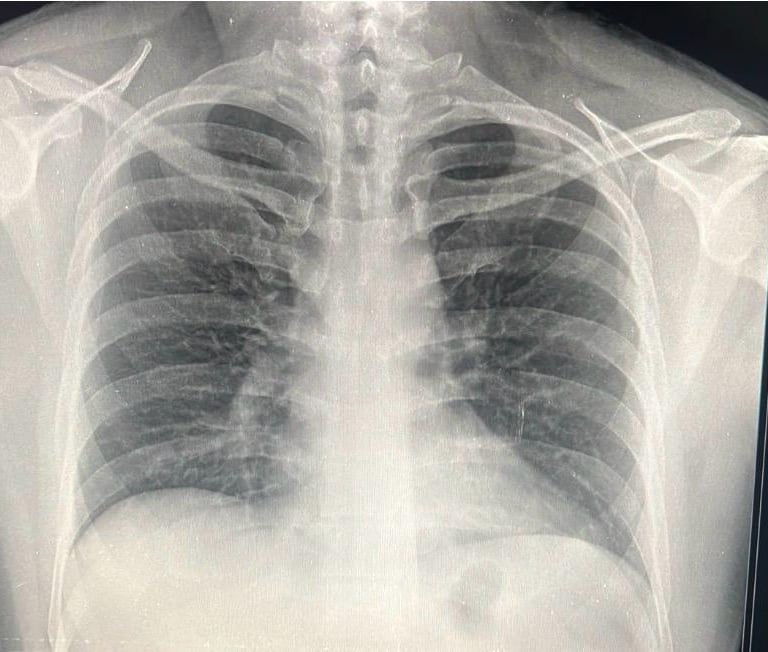

Radiografía Tórax

Estudios especializados para revisar el funcionamiento de los pulmones.